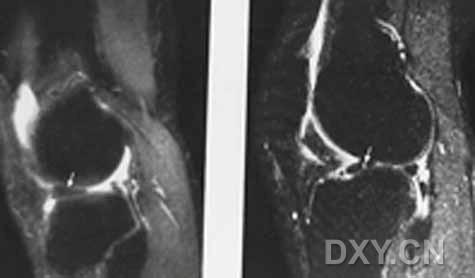

| 半月板囊肿 外侧半月板前角前缘1cm大小囊肿,合并外侧半月板前角的水平撕裂